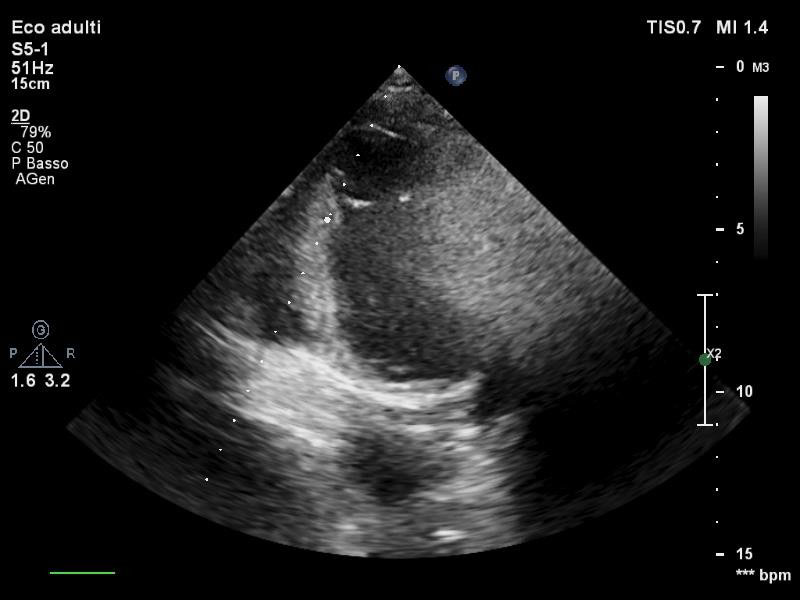

Post-procedural transthoracic echocardiography (TTE) showed a left ventricular ejection fraction (LVEF) of 20%, akinesia of interventricular septum, apical segments and left ventricular lateral wall and marked hypokinesis of the mid anterior wall. Right ventricular chamber resulted to be slightly dilated and pulmonary artery systolic pressure (PAPs) was roughly 50 mmHg. Inferior vena cava appeared dilated without respiratory collapse. Valvular apparatus presented no defects and pericardial effusions was absent. A chest X Ray did not detect any abnormalities. In consideration of signs of pulmonary hypertension, also associated with elevated transaminases levels (GPT 73 UI/l, GOT 213 UI/l), inhaled nitric oxide 20 ppm was added to the therapeutic approach.

During the third day after the event, the patient was weaned from mechanical ventilation and a TTE confirmed an improvement of systolic function with LVEF 30%, however no variations of kinesis abnormalities were found. Persistent good values of arterial blood pressure allowed a gradual decalage and suspension of intravenous inotropes as well as IABP removal. In the fifth day, a routine TTE revealed a thrombotic stratification in apical region and inferior apical wall of approximately 1.5 cm × 1.5 cm (Figure 3). At this point, it was necessary to exclude another possible diagnosis, such as the implant of an aberrant tendinous chord (Figure 4) linking the anterior and posterior apical segments, then, once the diagnosis of intra-cardiac thrombus was confirmed, unfractionated heparin infusion was started maintaining a range of aPTT between 50-70s. In the following two days echocardiographic follow up ascertained a significant reduction of the thrombosis reaching a complete resolution, then bridging with warfarin was initiated until INR > 2.

The patient was discharged 15 days after the event. At that time, TTE documented LVEF 35%, akinesis of interventricular septum and apical segments, hypokinesis of mid anterior wall. Right ventricular dimension and pulmonary pressure were normal. Therapy at discharge was based on loop diuretic, betablocker, angiotensin receptor blockers, potassium sparing diuretic, ivabradine and warfarin.